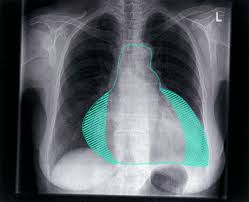

Pericardial effusion (per-e-KAHR-dee-ul uh-FU-zhun) is the buildup of too much fluid in the double-layered, saclike structure around the heart (pericardium). The space between these layers typically contains a thin layer of fluid. Lung cancer is the most common cause of the malignant pericardial effusion. Trauma: Blunt, penetrating, and iatrogenic injury to the myocardium, aorta, or coronary vessels can lead to the accumulation of blood within the pericardial sac.